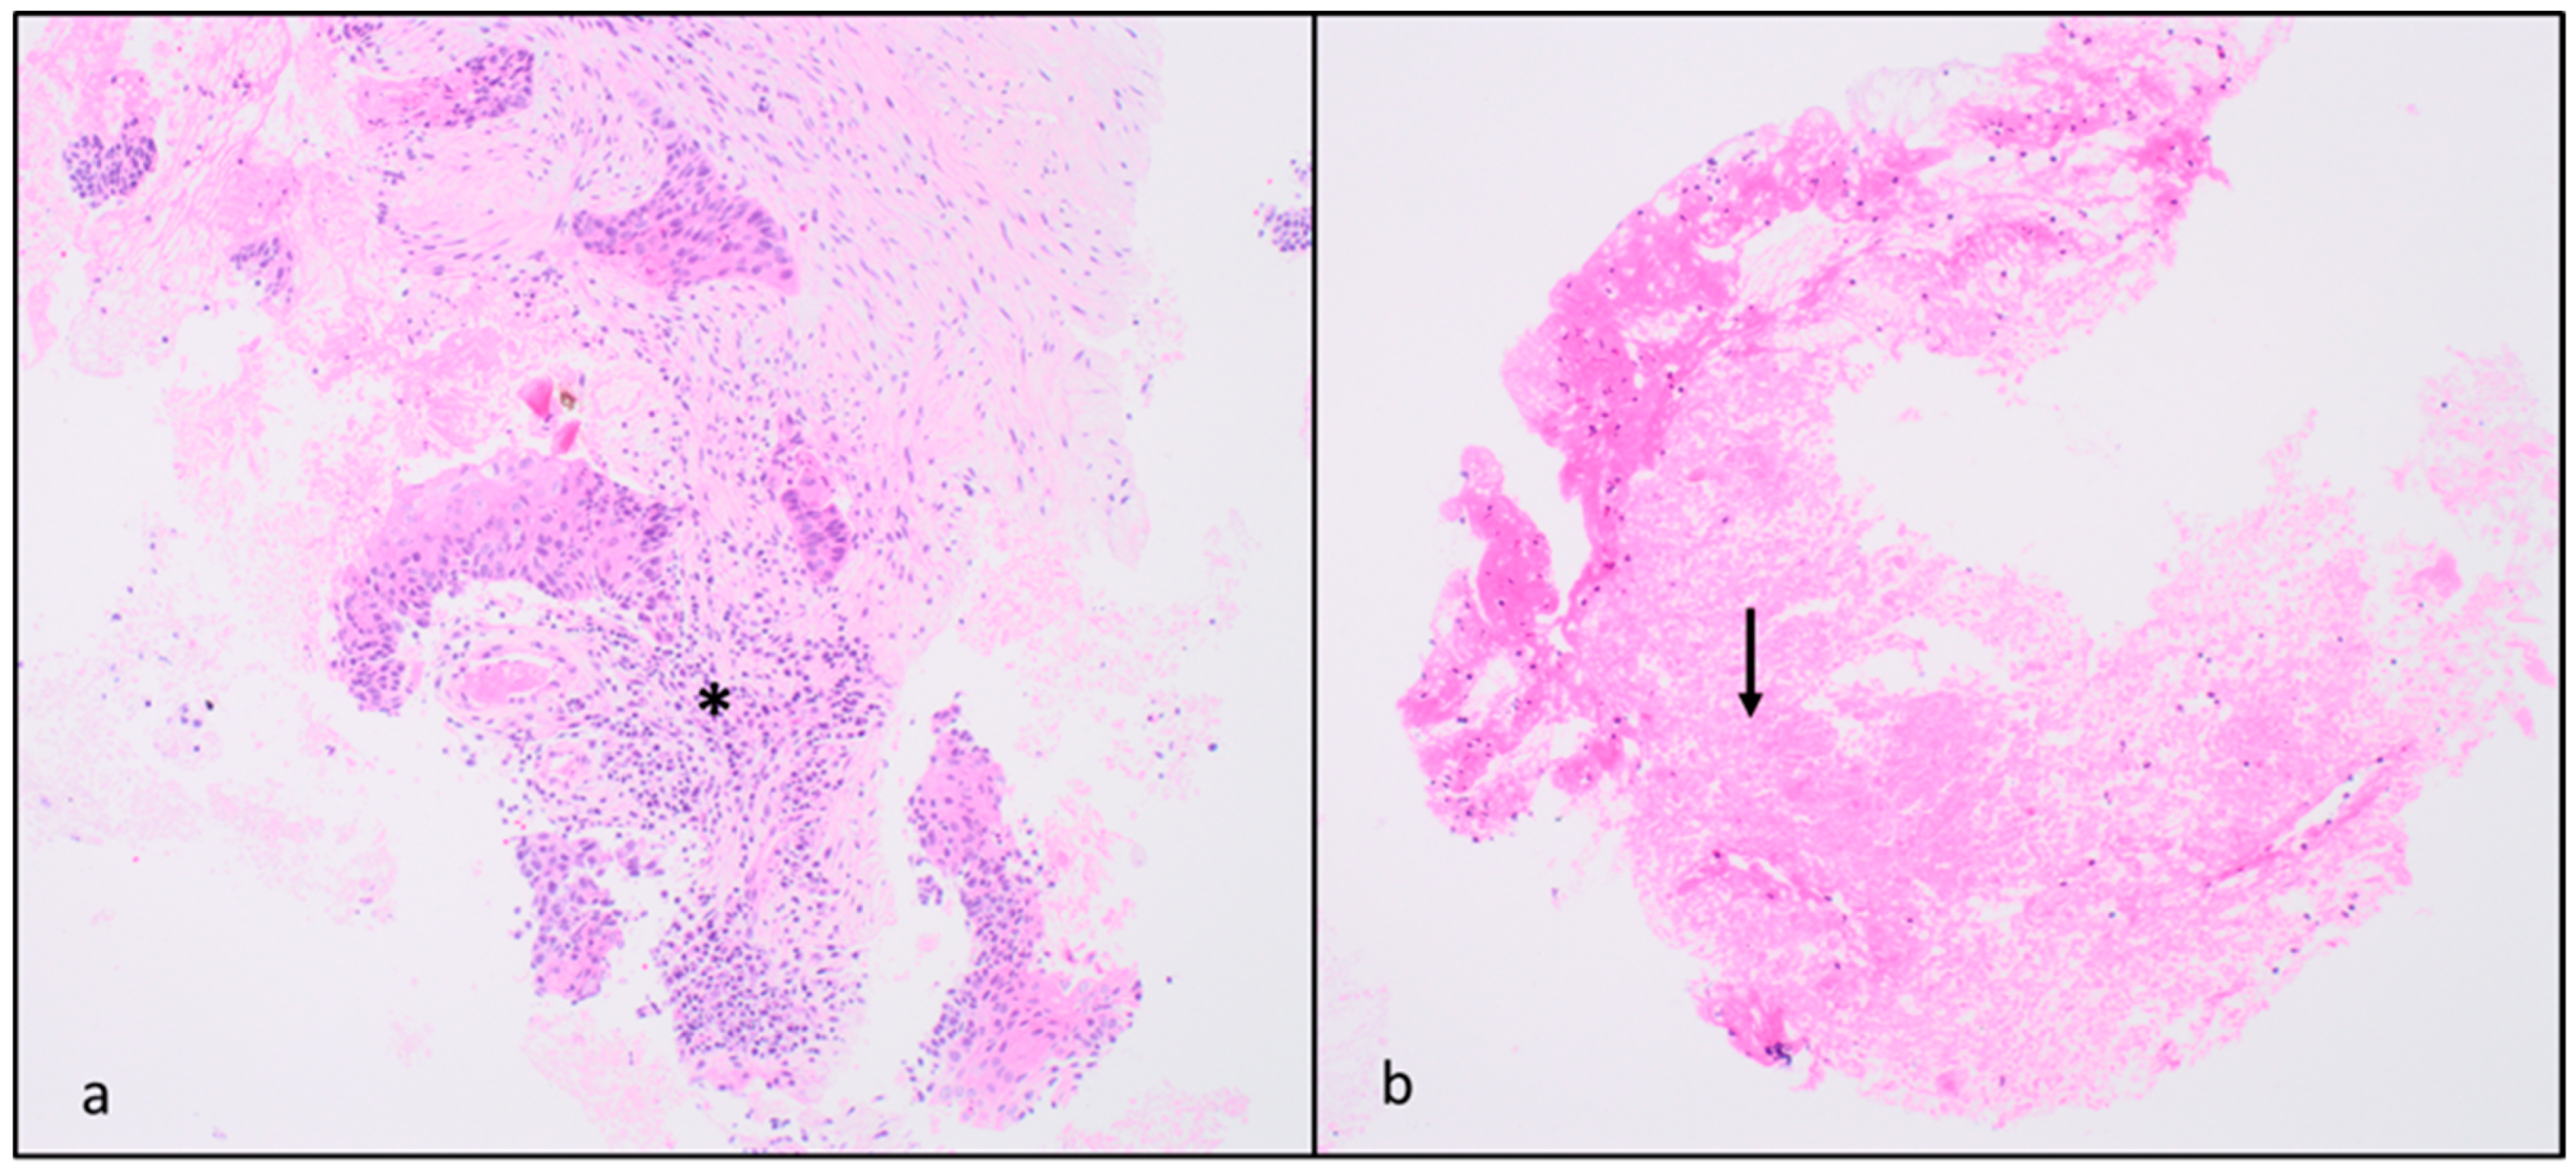

3. Results